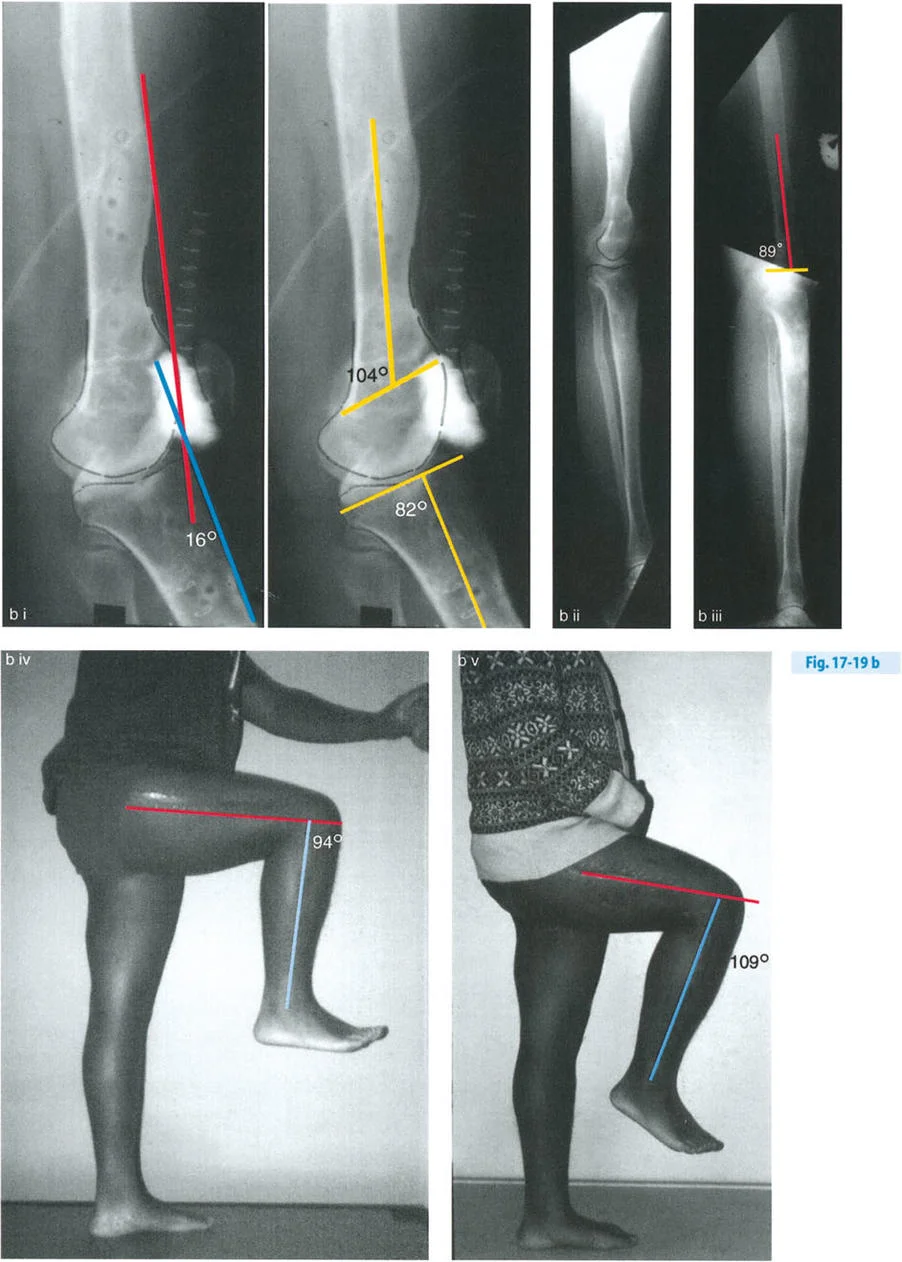

- حالة مريضة تبلغ من العمر 24 عامًا عانت من كسر في الفخذ في سن 12 عامًا، وعولجت بالشد. تسبب دبوس الشد في توقف نمو جزئي في الجزء القريب من عظم الساق، مما أدى إلى ارتداد ظنبوبي.

- تقييم مدى الحركة: يتم قياس مدى حركة الركبة، بما في ذلك أقصى تمدد وأقصى انثناء. يتم تحديد درجة فرط التمدد (HE - Hyperextension) أو درجة تقلص الانثناء الثابت (FFD - Fixed Flexion Deformity).

زوايا القياس الهامة:

- زاوية الانحناء البعيدة للفخذ (PDFA - Posterior Distal Femoral Angle): تقيس زاوية الجزء السفلي من عظم الفخذ. القيمة الطبيعية حوالي 84 درجة. الزيادة في هذه الزاوية (أكثر من 84 درجة) تشير إلى ارتداد فخذي.

- زاوية الانحناء القريبة للظنبوب (PPTA - Proximal Posterior Tibial Angle): تقيس زاوية الجزء العلوي من عظم الساق. القيمة الطبيعية حوالي 80 درجة. الزيادة في هذه الزاوية (أكثر من 80 درجة) تشير إلى ارتداد ظنبوبي.

- مركز دوران الزاوية (CORA - Center of Rotation of Angulation): يتم تحديد هذا النقطة على الأشعة السينية لتحديد مكان التشوه العظمي بدقة، وهو أمر بالغ الأهمية لتخطيط عملية قطع العظم.

تحليل الحالات المختلفة:

- الركبة الارتدادية بسبب الارتداد الفخذي:

- إذا كانت درجة فرط التمدد (HE) تساوي درجة الارتداد الفخذي (PDFA > 84°)، فهذا يعني أن التشوه كله ناتج عن عظم الفخذ.

- في هذه الحالة، يكون مركز CORA في الجزء البعيد من عظم الفخذ.

- الركبة الارتدادية بسبب الارتداد الظنبوبي:

- إذا كانت درجة فرط التمدد (HE) تساوي درجة الارتداد الظنبوبي (PPTA > 80°)، فهذا يعني أن التشوه كله ناتج عن عظم الساق.

- في هذه الحالة، يكون مركز CORA في الجزء القريب من عظم الساق.

- الركبة الارتدادية بسبب الارتداد الظنبوبي مع تقلص انثناء:

- إذا كان هناك ارتداد ظنبوبي (PPTA > 80°) ولكن لا يوجد فرط تمدد سريري (HE = 0°)، فهذا يشير إلى وجود تقلص انثناء مصاحب.

- إذا كان فرط التمدد (HE) أقل من درجة الارتداد الظنبوبي، فهذا يعني وجود تقلص انثناء جزئي.

- الركبة الارتدادية بسبب تشوه مركب (فخذي وظنبوبي):

- إذا كان هناك ارتداد في كل من الفخذ والساق، وكان مجموع درجتي الارتداد يساوي درجة فرط التمدد الكلي للركبة.

- إذا كان هناك تشوه مركب مع تقلص انثناء مصاحب، فقد يكون فرط التمدد السريري أقل من مجموع التشوهات العظمية.